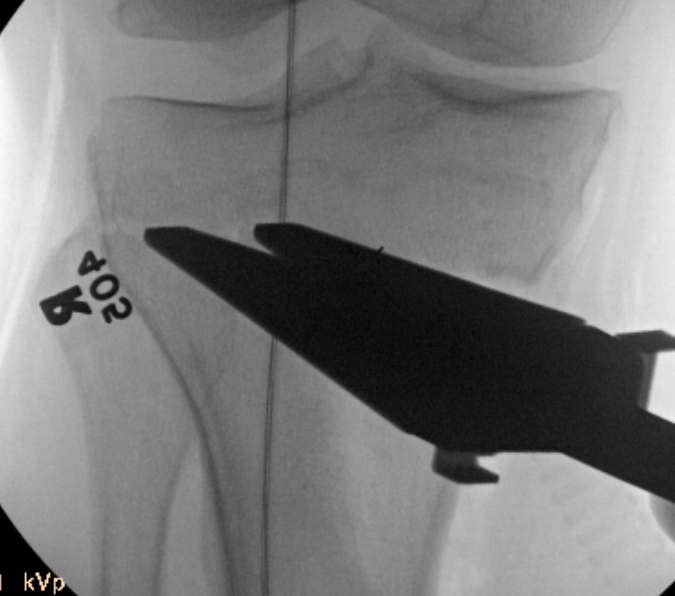

C. Intra-operative check

Use diathermy lead / drop rod

- center femoral head to center on talus

- ensure passes over lateral tibial spine / Fujisawa point